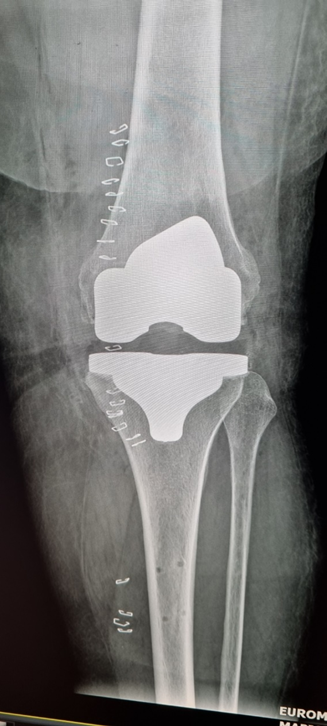

- Αποτέλεσμα: Ιδανική ανατομική και λειτουργική τοποθέτηση της πρόθεσης, με επιβεβαίωση σε πραγματικό χρόνο και μετεγχειρητική ακτινογραφική τεκμηρίωση της σωστής ευθυγράμμισης.

Μετεμφυτευτική αναπαράσταση και επιβεβαίωση της άριστης ανατομικά, αλλά και βιομηχανικά τοποθέτηση της νέας άρθρωσης

Μετεγχειρητική ακτινογραφία